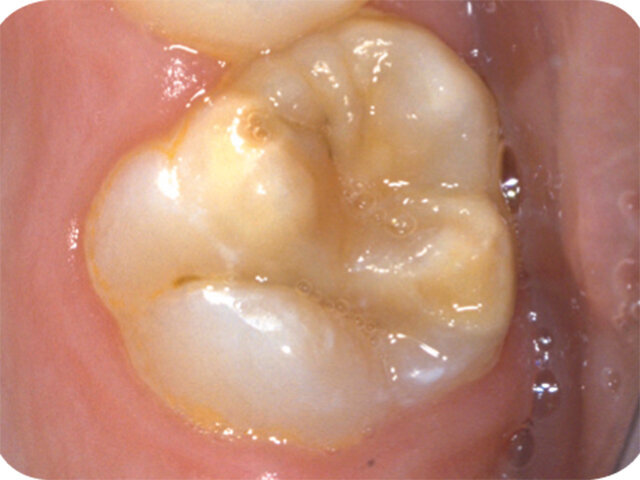

Molárová a incizální hypomineralizace skloviny (Molar Incisor Hypomineralisation – MIH) je globální problém postihující každé sedmé dítě. MIH je běžná vývojová porucha postihující především jeden nebo více prvních stálých molárů. Centrální řezáky mohou být rovněž postiženy, většinou však v menší míře. Může též dojít k hypomineralizaci druhých dočasných molárů (Hypomineralised Lesions on Second Primary Molars – HSPM, hypomineralizační léze druhých stálých molárů) nebo špičáků. U dětí s HSPM je až pětkrát vyšší pravděpodobnost vzniku MIH u stálého chrupu. Závažnost se velmi liší od mírných opacit k posterupčnímu odlomení skloviny.

Klinický vzhled

- Ohraničené opacity v rozpětí od krémově bílé, přes žlutou až po hnědé diskolorace

- Poškozená sklovina má normální tloušťku (dokud nedojde k posterupčnímu odlomení skloviny)

- Rychlá progrese zubního kazu

- Posterupční odlomení skloviny